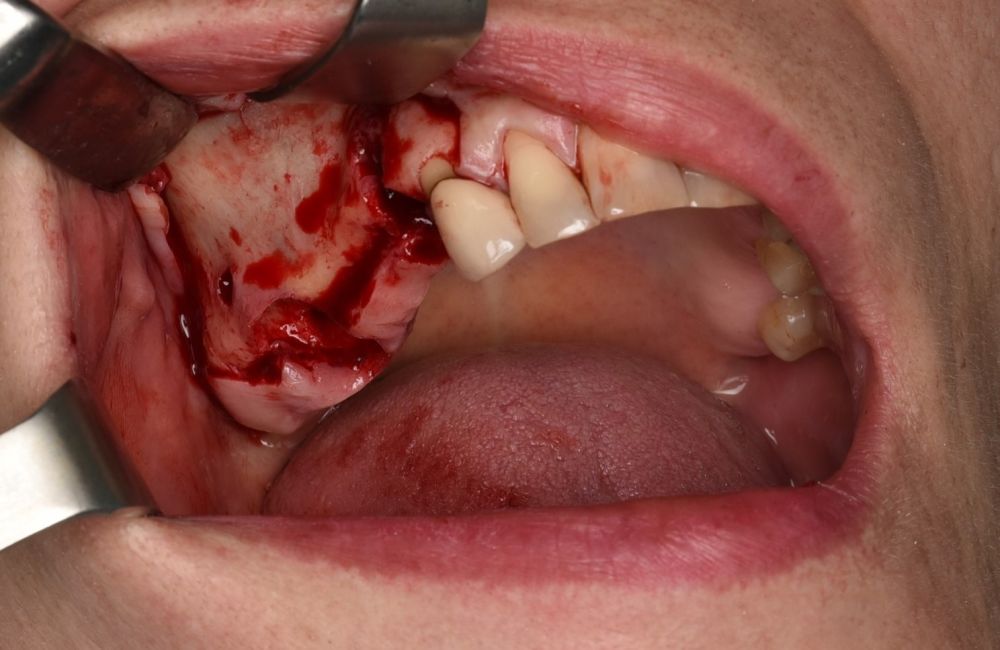

En la historia clínica, no se evidenciaron antecedentes médico-quirúrgicos de interés, alergias medicamentosas conocidas, ni hábitos tóxicos y no presentaba tratamiento médico habitual. Se observó a la exploración intraoral la movilidad de la prótesis fija y caries bajo las coronas con afectación radicular de los pilares 1.4 y 1.7 (Figura 1).

El abordaje quirúrgico del seno se realizó mediante un colgajo a espesor total trapezoidal con una incisión supracretal con descargas verticales vestibulares mesial a 1.3 y distal a 1.7 (Figura 5).